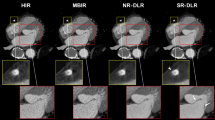

Deep learning reconstruction (DLR) is a new reconstruction method; it introduces deep convolutional neural networks into the reconstruction flow. This study was conducted in order to examine the clinical applicability of abdominal ultra-high-resolution CT (U-HRCT) exams reconstructed with a new DLR in comparison to hybrid and model-based iterative reconstruction (hybrid-IR, MBIR).

The image noise was significantly lower and the CNR was significantly higher on DLR than hybrid-IR and MBIR images (p < 0.01). DLR images received the highest and MBIR images the lowest scores for overall image quality.

DLR improved the quality of abdominal U-HRCT images.

• Image noise and overall image quality for hepatic ultra-high-resolution CT images improved with deep learning reconstruction as compared to hybrid- and model-based iterative reconstruction.